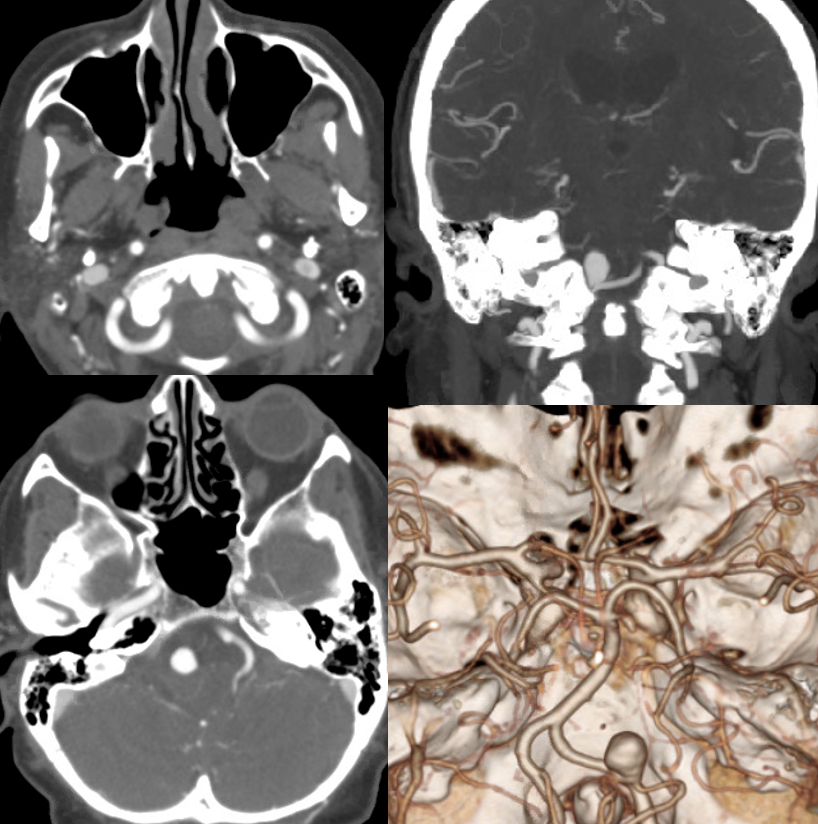

Mass effect/brainstem edema with a PICA aneurysm

Partially thrombosed even at smaller size is a sure sign of malignant / aggressive behavior